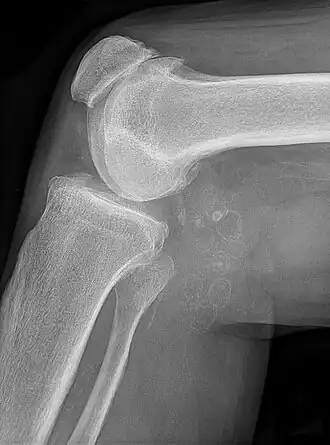

Chondromatose synoviale avec chondromes multiples dans le kyste de Baker, liés à une gonarthrose.

L'arthrose du genou est la cause la plus fréquente de douleur du genou après 50 ans. Elle peut se définir comme un amincissement de l'interligne fémoro-tibiale ou fémoro-patellaire, associé à une ostéophytose (prolifération osseuse exubérante) marginale tibiale ou fémorale et accessoirement à une ostéosclérose. La gonarthrose est la plus fréquente des arthroses (3 fois plus fréquente que la coxarthrose (Arthrose de hanche)). Elle est bilatérale dans 2/3 des cas. Dans certains cas, il s'agit d'une atteinte fémoro-tibiale interne. L'atteinte est bi-compartimentale, fémoro-tibiale interne et fémoro-patellaire dans 15 à 20 % des cas. L'âge moyen de survenue des douleurs chroniques est d'environ 65 ans.